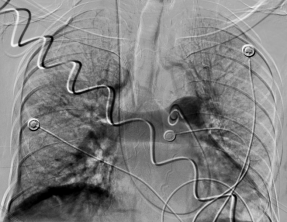

肺動(dòng)脈左右分支大量血栓(左邊血栓說(shuō)明) 下腔靜脈大范圍血栓(濾器置入攔截)(右圖血栓說(shuō)明)

十堰市人民醫(yī)院介入科迅速科內(nèi)會(huì)診,并制定周密、詳細(xì)的介入治療方案。術(shù)中,專家團(tuán)隊(duì)嚴(yán)格按照手術(shù)方案進(jìn)行手術(shù),第一步完成下腔靜脈濾器,攔截血栓,放射介入專家陳光斌、謝興武、李江山等專家團(tuán)隊(duì)全力以赴,在下腔靜脈情況不明,有無(wú)血栓無(wú)法再看的情況下,果斷采取從頸靜脈穿刺,下腔靜脈手推造影。而患者的嚴(yán)重程度讓多位專家倒吸一口涼氣,只見下腔靜脈中下段大塊血栓形成,栓頭鄰近雙腎靜脈,血栓隨時(shí)可能脫落。

見此情形,放射介入專家小心翼翼操作,將濾器死死卡住血栓頭,接下來(lái)就是第二步:完成肺動(dòng)脈開通。重癥醫(yī)學(xué)科專家加大氧流量,血管活性藥物穩(wěn)定血壓,為介入操作創(chuàng)造時(shí)間,同時(shí)介入專家豬尾巴導(dǎo)管上、導(dǎo)引導(dǎo)管上,不停進(jìn)行各段抽吸、取栓,經(jīng)過(guò)一個(gè)小時(shí)的精細(xì)操作,功夫不負(fù)有心人,雙肺動(dòng)脈干通了,主要肺動(dòng)脈分支通了,肺血管網(wǎng)明顯增多了,患者的情況也好轉(zhuǎn)了起來(lái)!也就意味著第二步操作成功!隨后的第三步,介入專家對(duì)下肢血栓進(jìn)行了抽吸、取栓,并置入溶栓導(dǎo)管進(jìn)行持續(xù)藥物灌注溶栓。又經(jīng)過(guò)兩個(gè)小時(shí),在兩科的密切合作下,整臺(tái)手術(shù)順利完成。

手術(shù)完幾個(gè)小時(shí),當(dāng)天下午就傳來(lái)好消息,患者生命體征明顯好轉(zhuǎn)。在放置導(dǎo)管的第三天,患者再次來(lái)介入科造影,發(fā)現(xiàn)肺栓塞基本消失,下肢血栓明顯消失,濾器繼續(xù)卡住下腔血栓!經(jīng)過(guò)多學(xué)科努力,通過(guò)綜合介入各種手段,重癥肺栓塞患者搶救成功!